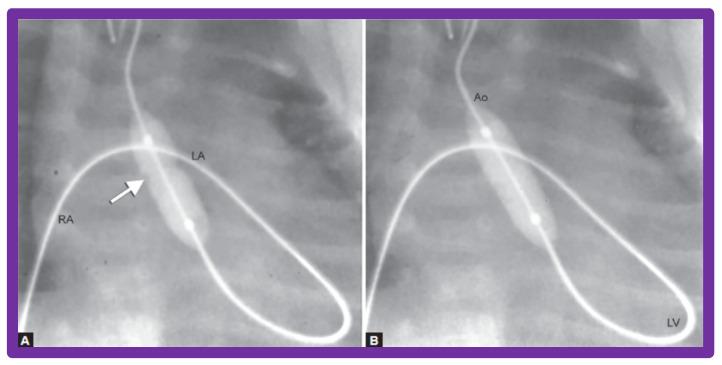

While investigating the outcomes of balloon dilatation procedures in patients with congenital obstructive lesions of the heart, several parallel observations were made. The purpose of this review is to present these observations/phenomena/innovations related to balloon dilatation of pulmonary stenosis (PS), aortic stenosis (AS), and aortic coarctation (AC). In subjects who had balloon pulmonary valvuloplasty (BPV), development of infundibular obstruction, electrocardiographic (ECG) changes, changes in right ventricular filling, role of balloon/annulus ratios on the results of BPV, and double balloon vs. single balloon BPV will be reviewed. In patients who had balloon aortic valvuloplasty (BAV), causes of aortic insufficiency and trans-umbilical venous approach for BAV are tackled. In children who had balloon angioplasty (BA) of AC, aortic remodeling and biophysical response after BA of AC are discussed.

在研究患有先天性心脏阻塞性病变患者的球囊扩张手术结果时,进行了几项平行观察。本综述的目的是介绍这些与肺动脉狭窄(PS)、主动脉狭窄(AS)和主动脉缩窄(AC)球囊扩张相关的观察结果/现象/创新。在接受球囊肺动脉瓣成形术(BPV)的受试者中,将对漏斗部梗阻的发展、心电图(ECG)变化、右心室充盈变化、球囊/瓣环比率对BPV结果的作用以及双球囊与单球囊BPV进行综述。在接受球囊主动脉瓣成形术(BAV)的患者中,探讨主动脉瓣关闭不全的原因以及BAV的经脐静脉途径。在接受AC球囊血管成形术(BA)的儿童中,讨论AC球囊血管成形术后的主动脉重塑和生物物理反应。